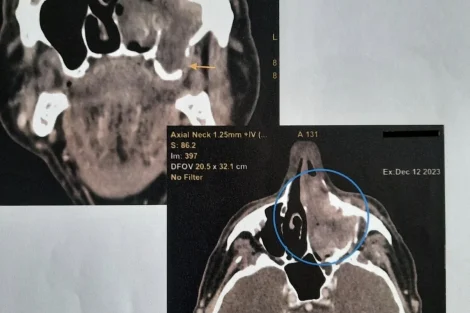

Nedim Leto je na čelu multidisciplinarnog tima, a u razgovoru za Klix.ba je kazao da se ove operacije izvode na teškim onkološkim pacijentima sa uznapredovanim karcinomima glave, lica i vrata.

Dodao je da pacijenti dobivaju kvalitetan tretman u ovoj ustanovi te da je osim uklanjanja tumora jako važna i rekonstrukcija defekta koja se radi lokalnim ili udaljenim režnjevima (deltopektoralni, pektorali, temporalnim mišićem) te slobodnim koštanim graftovima sa kriste ilijake i rebra.

“Na taj način defekt se pokriva u cjelosti i ne izaziva nakaznost postoperativnu nakon radikalnog uklanjanja tumora već pacijent anatomskomorfološki zadržava svoj izgled što doprinosi boljem kvalitetu života postoperativno, ali i omogućava pacijentima lakši i brzi oporavak. Jako je važna i postoperativna njega koja se vrši na Jedinici za intenzivnu njegu uz stalni monitoring i odgovarajući medikamentozni tretman od anesteziologa koji su veoma bitni u ovom čitavom procesu, kao i preostali dio tima”, dodao je Leto.